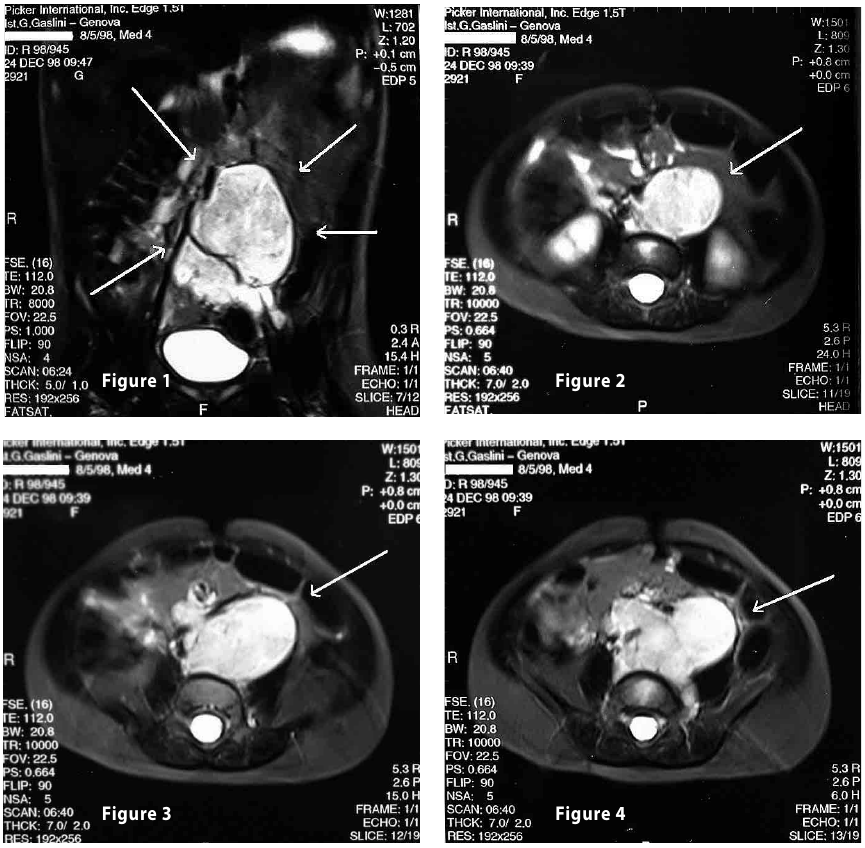

Complete objective response of neuroblastoma to biological treatment.

Figure1

Figure2

Figure3

Figure4